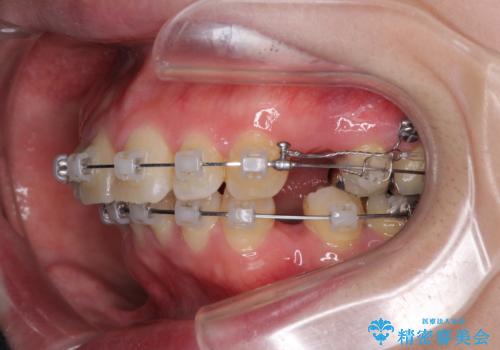

- クリアブラケット

- 2年2ヶ月

上下左右の歯を1本ずつ、合計4本抜歯して、ワイヤーにて矯正することとなりました。

もともと下の前歯の永久歯が1本欠損しており、抜歯部位の選択を考慮しなければならない症例でした。シミュレーションを事前に行い、下顎の抜歯部位を決定しました。